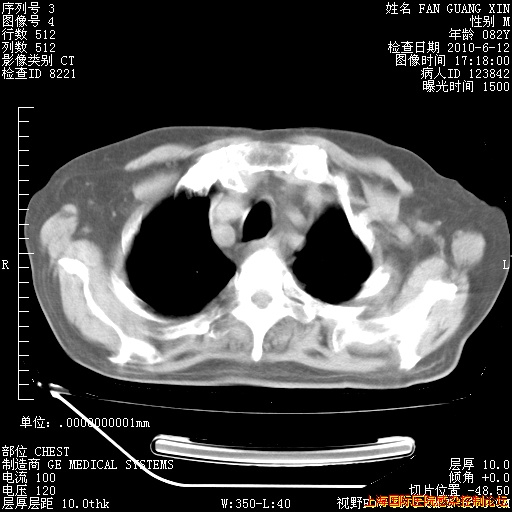

今天复查CT

今天CT

整整相隔30天的肺部CT好像有所好转啊。甲强龙减量第3天,需要观察体温。

海管,自昨日你和我通完话后,不知您岳父消化道症状有无缓解?体温怎样?阅读7.12日胸部ct,个人认为目前激素治疗是有效的,甲强龙减量是适宜的。因在抗痨治疗,需密切观察肝功、肾功能和血常规。不过,老年、长期住院和大量使用激素,很担心菌群失调发生